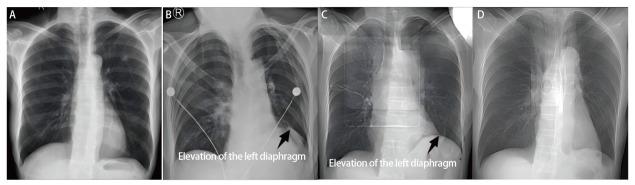

The baseline clinical characteristics were comparable between the two groups (P>0.05). The incidence of pulmonary air leakage at 24 h after surgery (31.5% vs 29.6%) and the incidence of postoperative PAL (20.4% vs 14.8%) showed no significant differences between the two groups (P>0.05). The intraoperative air leak test to 24 hours after surgery revealed that air leakage ceased in 8 cases (32.0%) in the control group, compared to 14 cases (46.7%) in the experimental group. Moreover, during the progression from air leakage at 24 hours post-surgery to postoperative PAL, air leakage ceased in 6 cases (35.3%) in the control group and 8 cases (50.0%) in the experimental group, with a statistically significant difference (P<0.001). Compared to the control group, the patients in the experimental group exhibited more pronounced postoperative diaphragmatic elevation that recovered to a slightly higher than preoperative level by 3 mon after surgery.

两组患者的基线临床特征具有可比性(P>0.05)。术后24小时肺漏气发生率(31.5%对29.6%)和术后PAL发生率(20.4%对14.8%)在两组之间无显著差异(P>0.05)。术中漏气试验至术后24小时显示,对照组有8例(32.0%)漏气停止,试验组为14例(46.7%)。此外,在从术后24小时漏气进展至术后PAL的过程中,对照组有6例(35.3%)漏气停止,试验组为8例(50.0%),差异有统计学意义(P<0.001)。与对照组相比,试验组患者术后膈肌抬高更明显,术后3个月恢复至略高于术前水平。